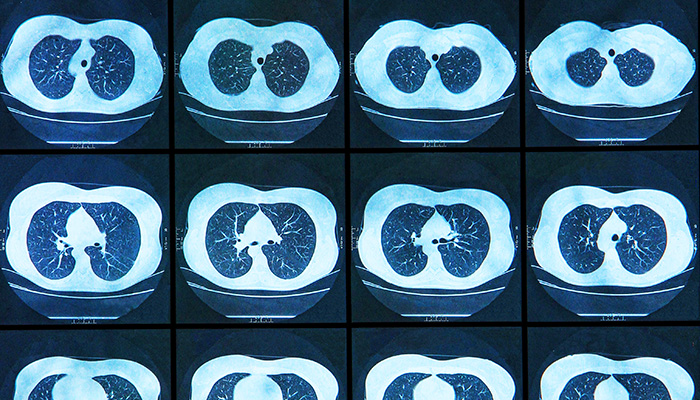

The Brigham and Women’s Hospital Severe Asthma Program, part of the Mass General Brigham Asthma Center, provides state-of-the-art diagnostic and therapeutic options to improve the respiratory health of patients with severe asthma